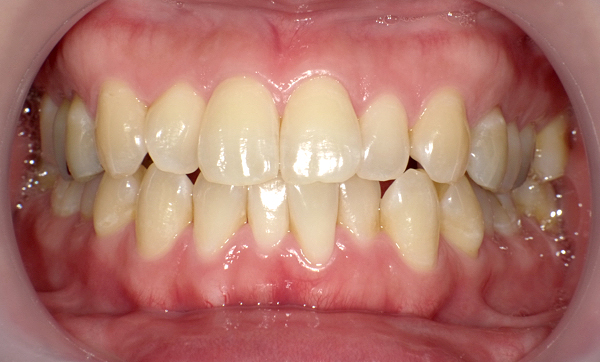

症例_008 「上下の前歯」症例

治療期間:13ヶ月金額:57万円+税40代女性捻転歯前歯のガタガタ

Before | After |